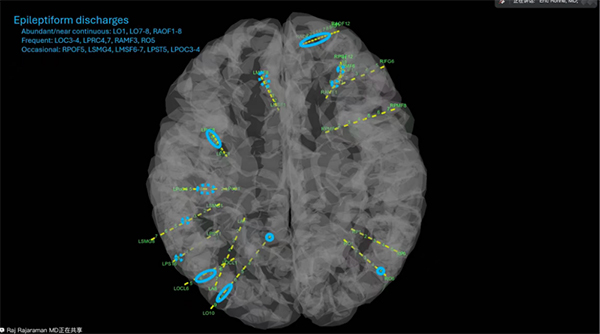

北京儿童医院癫痫中心团队,来自功能神经外科、神经内科、神经电生理、神经影像等专家率先分享复杂儿童癫痫病例,呈现了从患儿现病史梳理、多维度术前评估,到外科治疗方案制定与术后管理的全诊疗闭环。团队结合患儿临床发作表现、发作期脑电特征,联动头颅CT、核磁及融合影像等技术,精准定位癫痫发作起源于左额顶区域,针对性设计SEEG(立体定向脑电图)电极置入计划,最终成功找到致痫灶并完成切除,既有效降低了多次手术对患儿的身心创伤,也减轻了患者家庭经济负担,充分体现“精准诊疗+人文关怀” 双重理念。